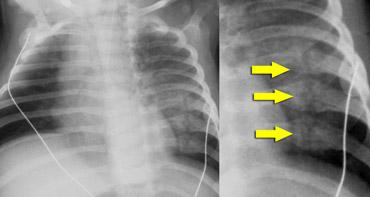

Gãy xương sườn

Trong hành vi lắc mạnh, đứa trẻ bị giữ rất chặt quanh ngực và bị siết chặt trong khi bị lắc.

Điều này nén các xương sườn theo hướng trước-sau và có xu hướng làm gãy chúng ở vị trí gần chỗ bám vào đốt sống và ở phía bên, nơi chúng gần như bị gập đôi.

Do cơ chế chấn thương đặc thù này, gãy xương sườn bên và sau có độ đặc hiệu cao đối với lạm dụng.

Những gãy xương sườn này ở trẻ bị lạm dụng có thể được phát hiện tình cờ trên phim X-quang ngực được chụp vì lý do khác, chẳng hạn như đánh giá viêm phổi.

Gãy xương sườn có độ đặc hiệu cao đối với lạm dụng.

Trong một nghiên cứu tại Hà Lan, tổng cộng 254 gãy xương được tìm thấy trong 56 trường hợp chấn thương đầu do lạm dụng. Tỷ lệ gãy xương sườn và gãy xương hành xương cực kỳ cao (tài liệu tham khảo).

Gãy xương sườn gặp khó khăn tương tự như tổn thương hành xương ở chỗ chúng dễ bị bỏ sót trên phim X-quang.

Trong giai đoạn cấp tính, chúng không rõ ràng trên phim X-quang vì ít có sự di lệch.

Chúng thường được xác định trên phim khảo sát xương toàn thân lặp lại khi các gãy xương đang trong giai đoạn lành, biểu hiện bằng hình ảnh can xương.

Hình ảnh

Trẻ được đánh giá vì khối mô mềm vùng sụn-xương sườn. Siêu âm cho thấy phù nề mô mềm (mũi tên vàng), phần sụn của xương sườn (mũi tên đỏ) bị tách rời khỏi phần xương (mũi tên cam) của xương sườn. Phim ngực ban đầu âm tính. Phim ngực chụp lại 2 tuần sau cho thấy các gãy xương.